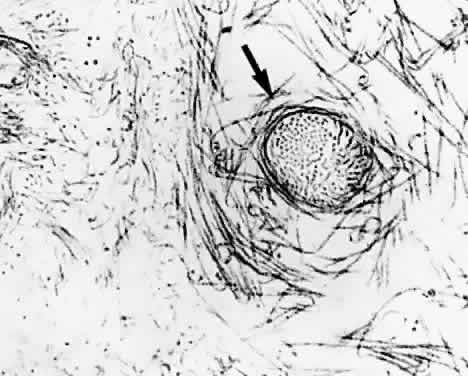

Vitreoretinal Interface

The periphery of the vitreous body, known as the vitreous cortex, courses anteriorly and posteriorly from the vitreous base. The portion that courses forward and inward from the vitreous base is called the anterior vitreous cortex. The portion coursing posteriorly from the posterior border of the vitreous base is known as the posterior vitreous cortex. The posterior vitreous cortex is 100 to 110 μm thick and consists of densely packed type II collagen fibrils (Fig. 15) and other extracellular matrix components. Contrary to previous beliefs, there are no direct connections between the posterior vitreous cortex and the retina, yet the posterior vitreous cortex is adherent to the internal limiting lamina (ILL) of the retina, especially in youth (Fig. 16). The exact nature of the adhesion between the posterior vitreous cortex and the ILL is not known but most probably results from the action of the various extracellular matrix molecules found at this interface.147,148

Fig. 15. Ultrastructure of human posterior vitreous cortex. Scanning electron micrograph of the posterior aspect of the posterior vitreous cortex demonstrates dense packing of type II collagen fibrils. The density is somewhat exaggerated by the dehydration performed during specimen preparation for electron microscopy. Bar = 10 μm.

Fig. 16. Vitreoretinal interface in youth. A: Dark-field microscopy of the posterior vitreous in a 14-year-old boy. The sclera, choroid, and retina were dissected off the corpus vitreus, which remains attached to the anterior segment. In contrast to adults, there is an extra layer of tissue that remained adherent to the posterior vitreous cortex when the retina was dissected off. The white arrow indicates the location of the fovea. The circular structure below this location is the prepapillary hole in the posterior vitreous cortex. Emanating from this hole are linear, branching structures (black arrows) that correspond to the location of the retinal vessels. B: Scanning electron microscopy of the tissue described in (A) demonstrates many round structures adherent to the posterior aspect of the tissue. Bar = 10 μm. C: Higher magnification showing the attachment of one of these round structures. There appears to be an indentation or hole on the posterior aspect of this structure. Bar = 1 μm. D: Transmission electron microscopy of this specimen identifies this tissue as the internal limiting lamina (ILL) of the retina attached to the posterior vitreous cortex. The round structures are identified as the inner portion of Müller cells that remained adherent to the posterior aspect of the ILL, with a hole on the posterior aspect of the inner portion of the Müller cell where it was torn away from the rest of the cell body (×20,800). (From Sebag J. Age-related differences in the human vitreoretinal interface. Arch Ophthalmol 109:966, 1991, with permission)

When the posterior vitreous is detached from the retina, a hole in the prepapillary vitreous cortex can often be seen (Fig. 17A). If peripapillary glial tissue is torn away during PVD and remains attached to the vitreous cortex surrounding the prepapillary hole, it is referred to as Vogt's or Weiss's ring. Vitreous can extrude through the prepapillary hole in the vitreous cortex (see Fig. 12A) but does so to a lesser extent than through the premacular vitreous cortex (see Fig. 12B and D). Various vitreomaculopathies can result from anteroposterior traction.148,149 Other mechanisms, particularly tangential vitreomacular traction,149,150 have been implicated in the pathogenesis of macular holes.